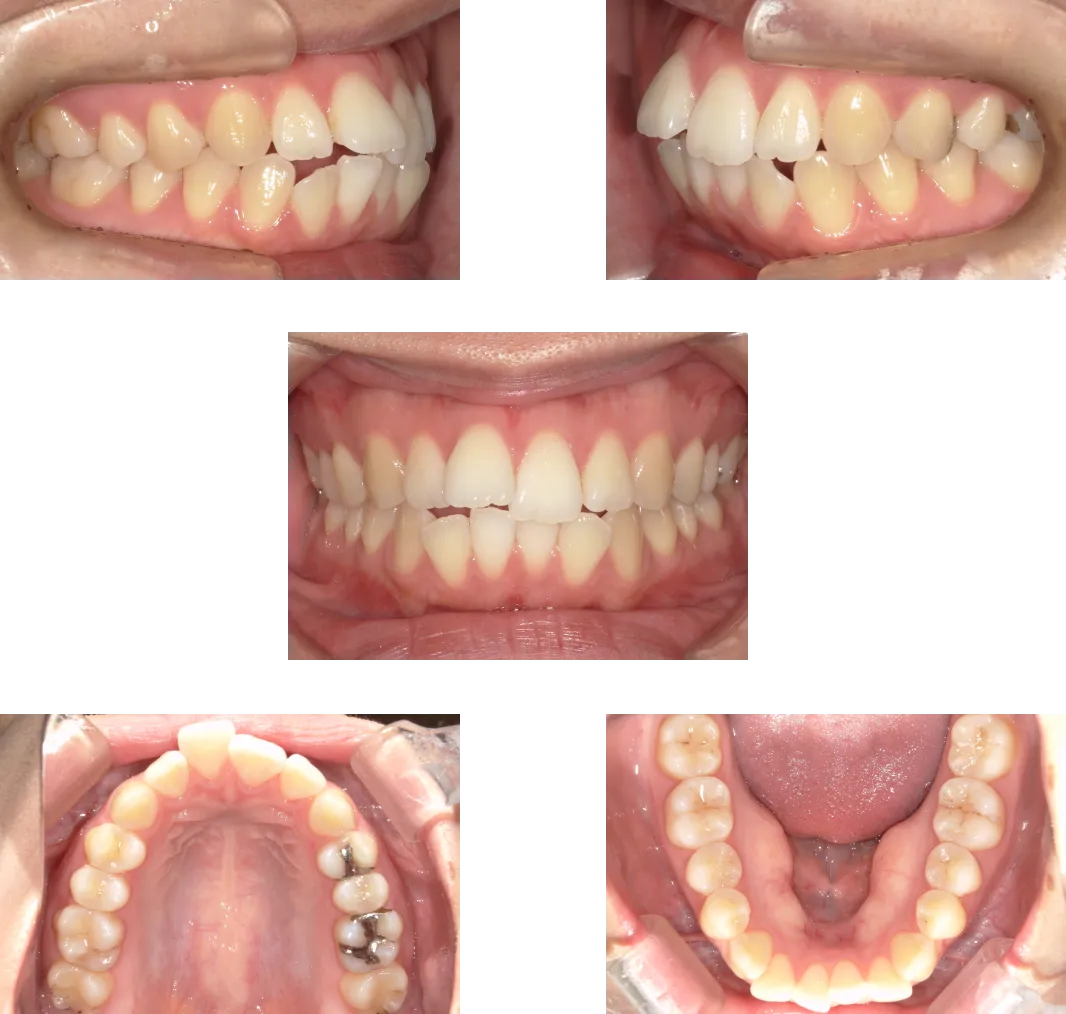

叢生 -39歳-

• Before

• After

診断

両側顎関節の変形

治療期間

1年6ヶ月+保定期間2年

料金

1,060,000円

抜歯

なし

リスク

痛み、軽度の歯根吸収、術後の変化